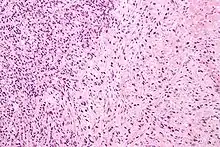

Gleason Pattern 3. H&E stain.

• Pattern 3 - The tissue still has recognizable glands, but the cells are darker. At high magnification, some of these cells have left the glands and are beginning to invade the surrounding tissue or having an infiltrative pattern. This corresponds to a moderately differentiated carcinoma.

Gleason 3 is a clearly infiltrative neoplasm, with extension into adjacent healthy prostate tissue. The glands alternate in size and shape, and are often long/angular. They are usually small/micro-glandular in comparison to Gleason 1 or 2 grades. However, some may be medium to large in size. The small glands of Gleason 3, in comparison to the small and poorly defined glands of pattern 4, are distinct glandular units. Mentally you could draw a circle around each of the glandular units in Gleason 3.[4][7]